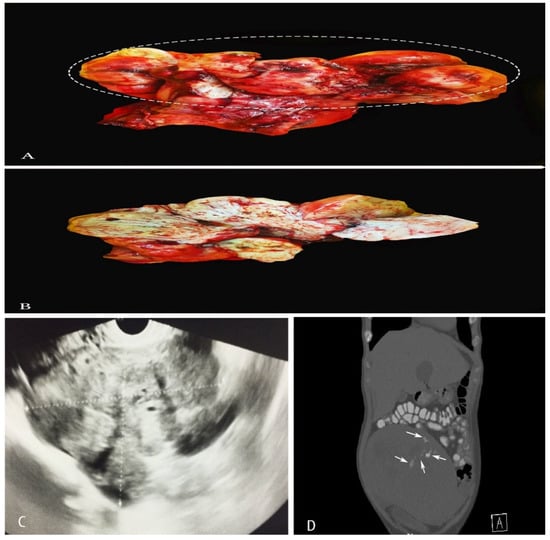

Imaging Modalities

3.1.3. Pathology